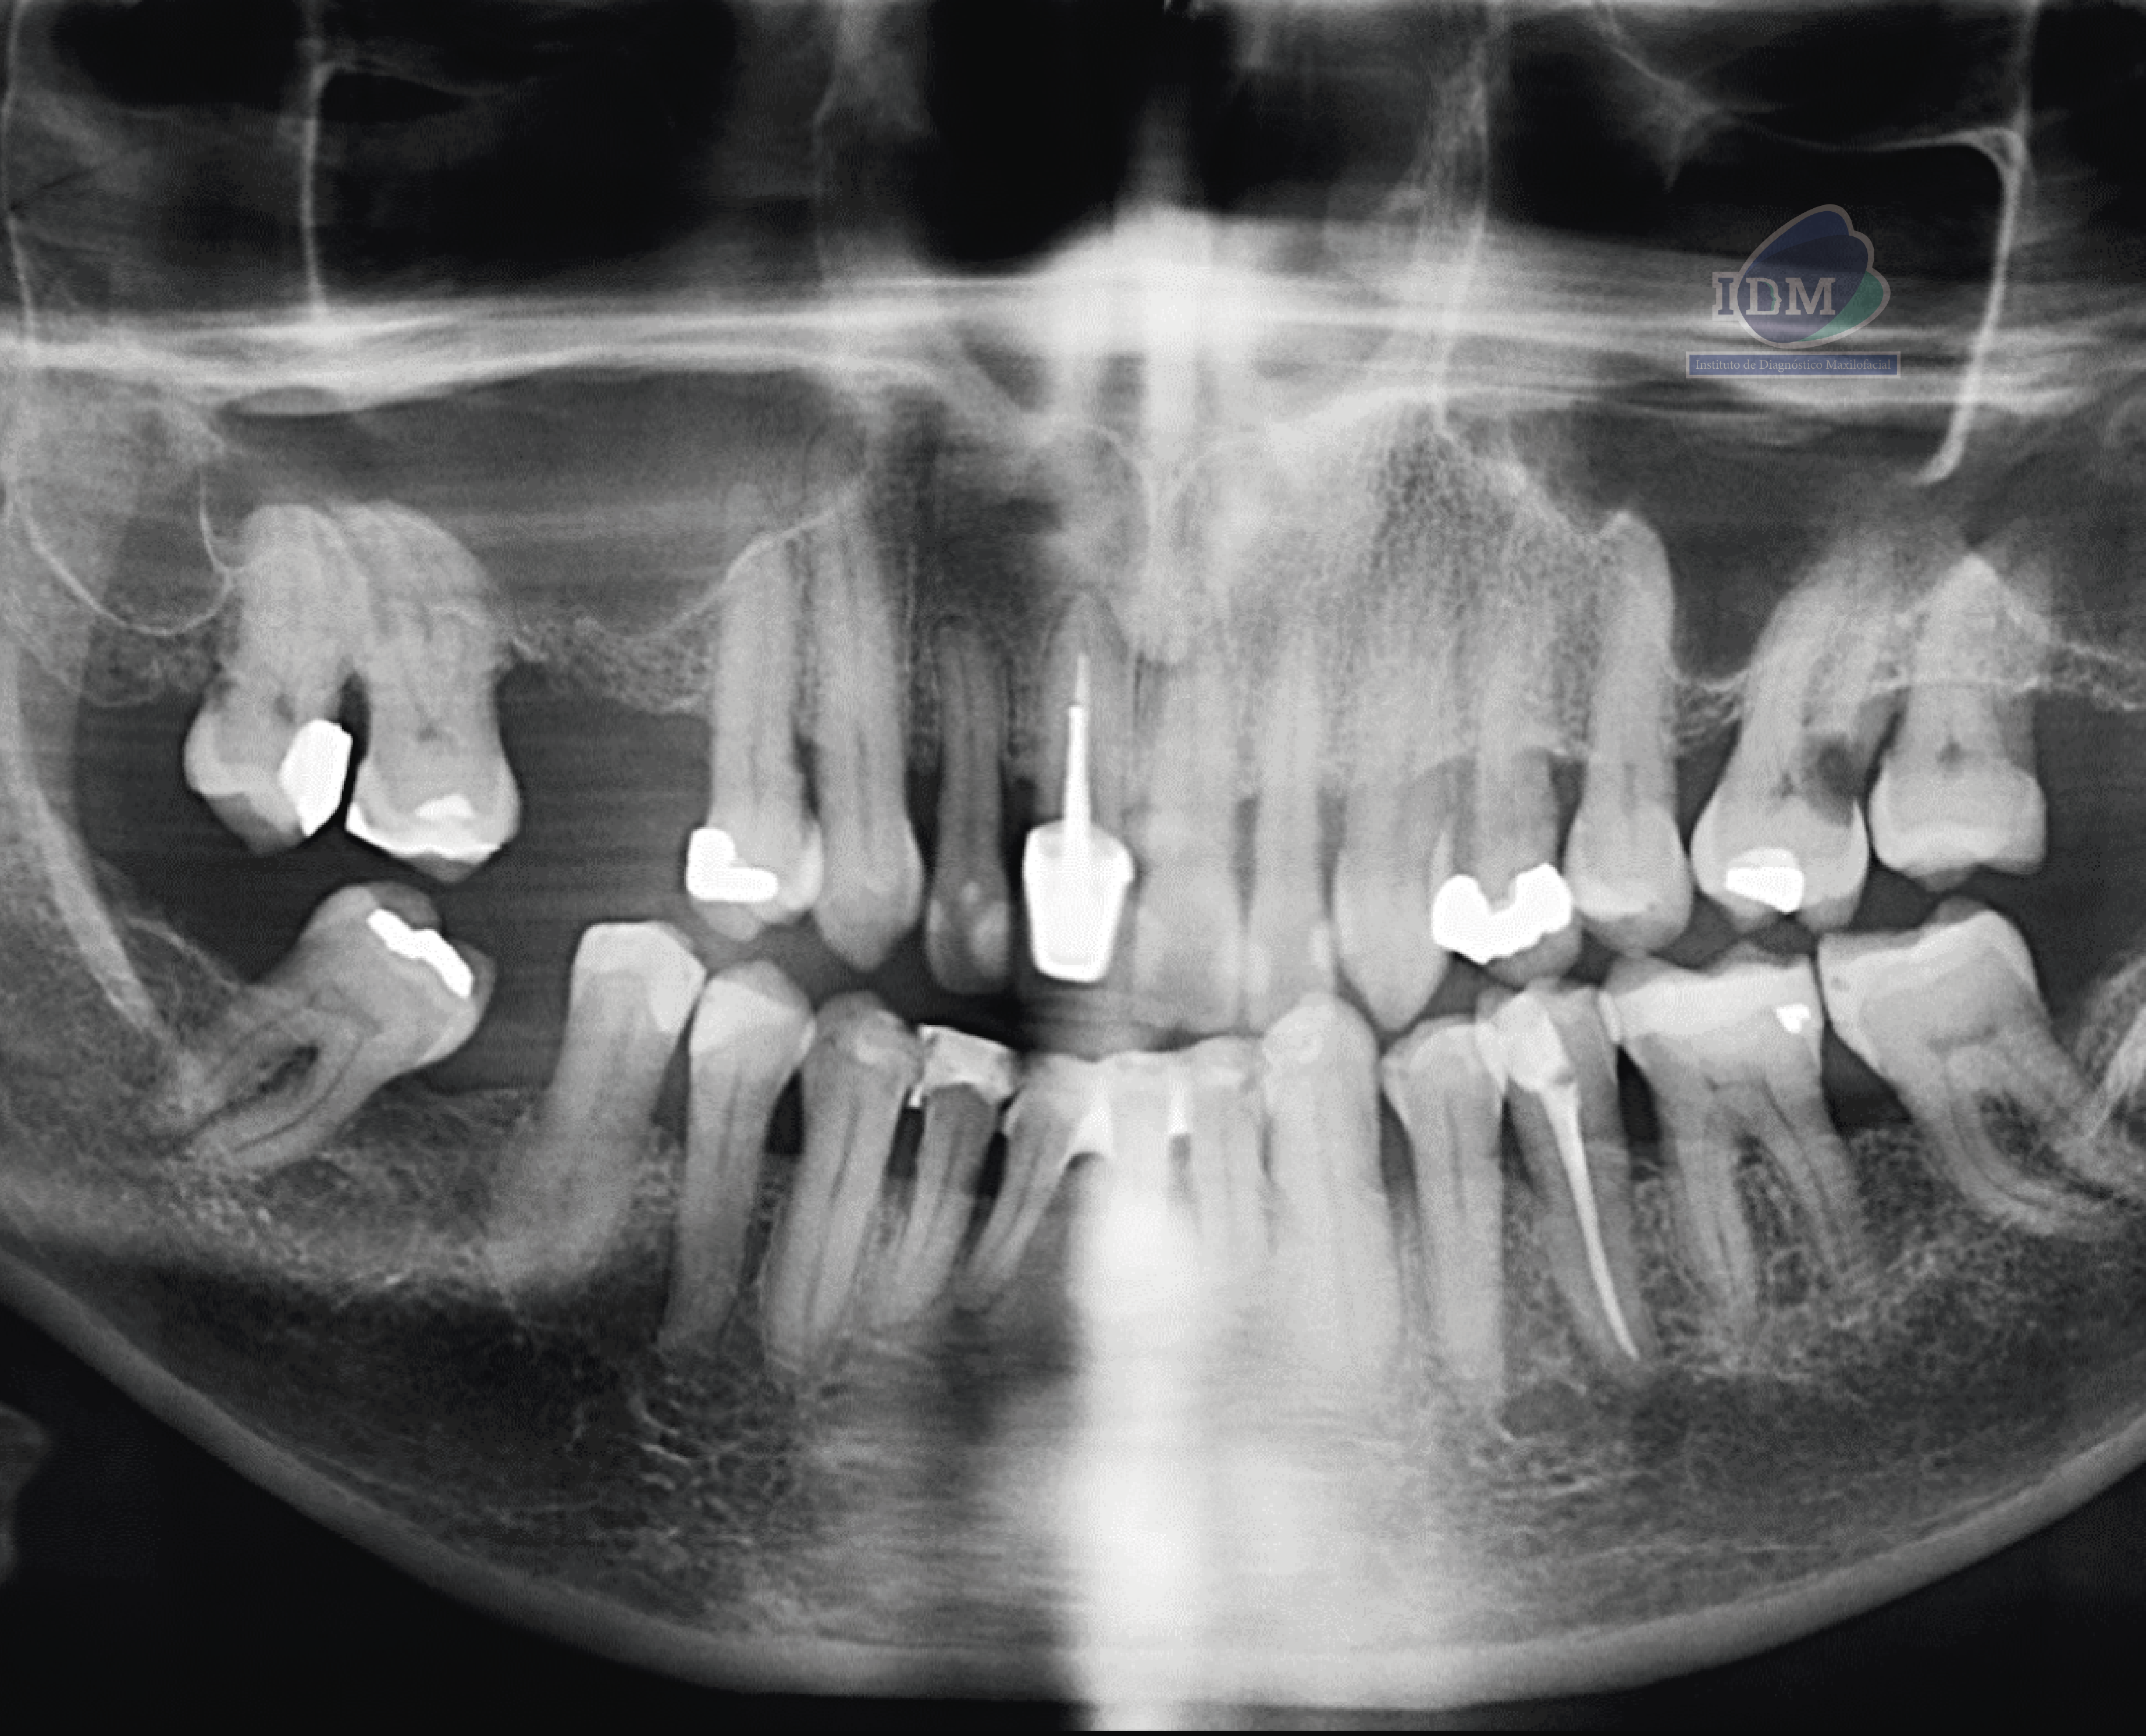

Paciente masculino de 70 años de edad acude a IDM- Sede Miraflores para realizarse una tomografía por un dolor leve que sentía en el primer cuadrante, a la evaluación de la radiografía panorámica se observa edentulismo parcial, la neumatización de ambos senos maxilares, reabsorción ósea moderada del proceso alveolar, las piezas 18 y 17 con restauraciones coronarias amplias, así como piezas dentales con tratamiento de conductos (subextendida en la pieza 11) y la presencia de una lesión cariosa cervicodistal amplia en la pieza 26.

Radiografia Panorámica